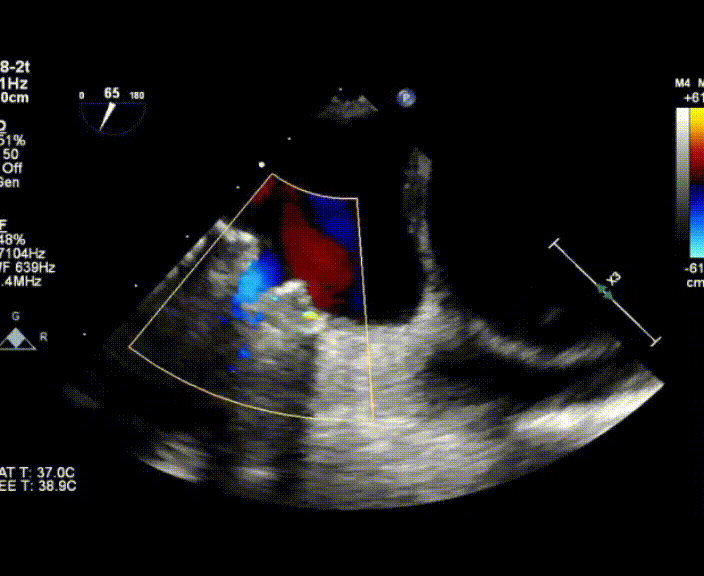

超聲心動(dòng)圖提示:右心增大,右室肥厚,左室測(cè)值偏小,房間隔中份探及修補(bǔ)術(shù)后回聲,房水平未見殘余分流,三尖瓣重度反流,重度肺動(dòng)脈高壓,中度肺動(dòng)脈瓣反流,左室收縮功能測(cè)值正常,右室收縮功能減低 。

術(shù)中首先在局麻下穿刺股動(dòng)脈、股靜脈,完成心導(dǎo)管檢查評(píng)估后轉(zhuǎn)為全麻,在食道超聲引導(dǎo)下穿刺房間隔,穿刺成功后將加硬導(dǎo)絲送入左上肺靜脈建立軌道,根據(jù)患者病情行球囊預(yù)擴(kuò)張后植入6mm孔徑房間隔造孔支架,經(jīng)透視及食道超聲評(píng)估支架左右盤展開良好,夾持于房間隔兩側(cè),固定穩(wěn)定、位置良好,食道彩超顯示房水平右向左為主分流,分流孔直徑符合預(yù)期大小,心導(dǎo)管檢查評(píng)估達(dá)到預(yù)期效果,釋放造孔支架。術(shù)后12h患者下床活動(dòng),恢復(fù)順利,擬于近日完善術(shù)后評(píng)估后出院。